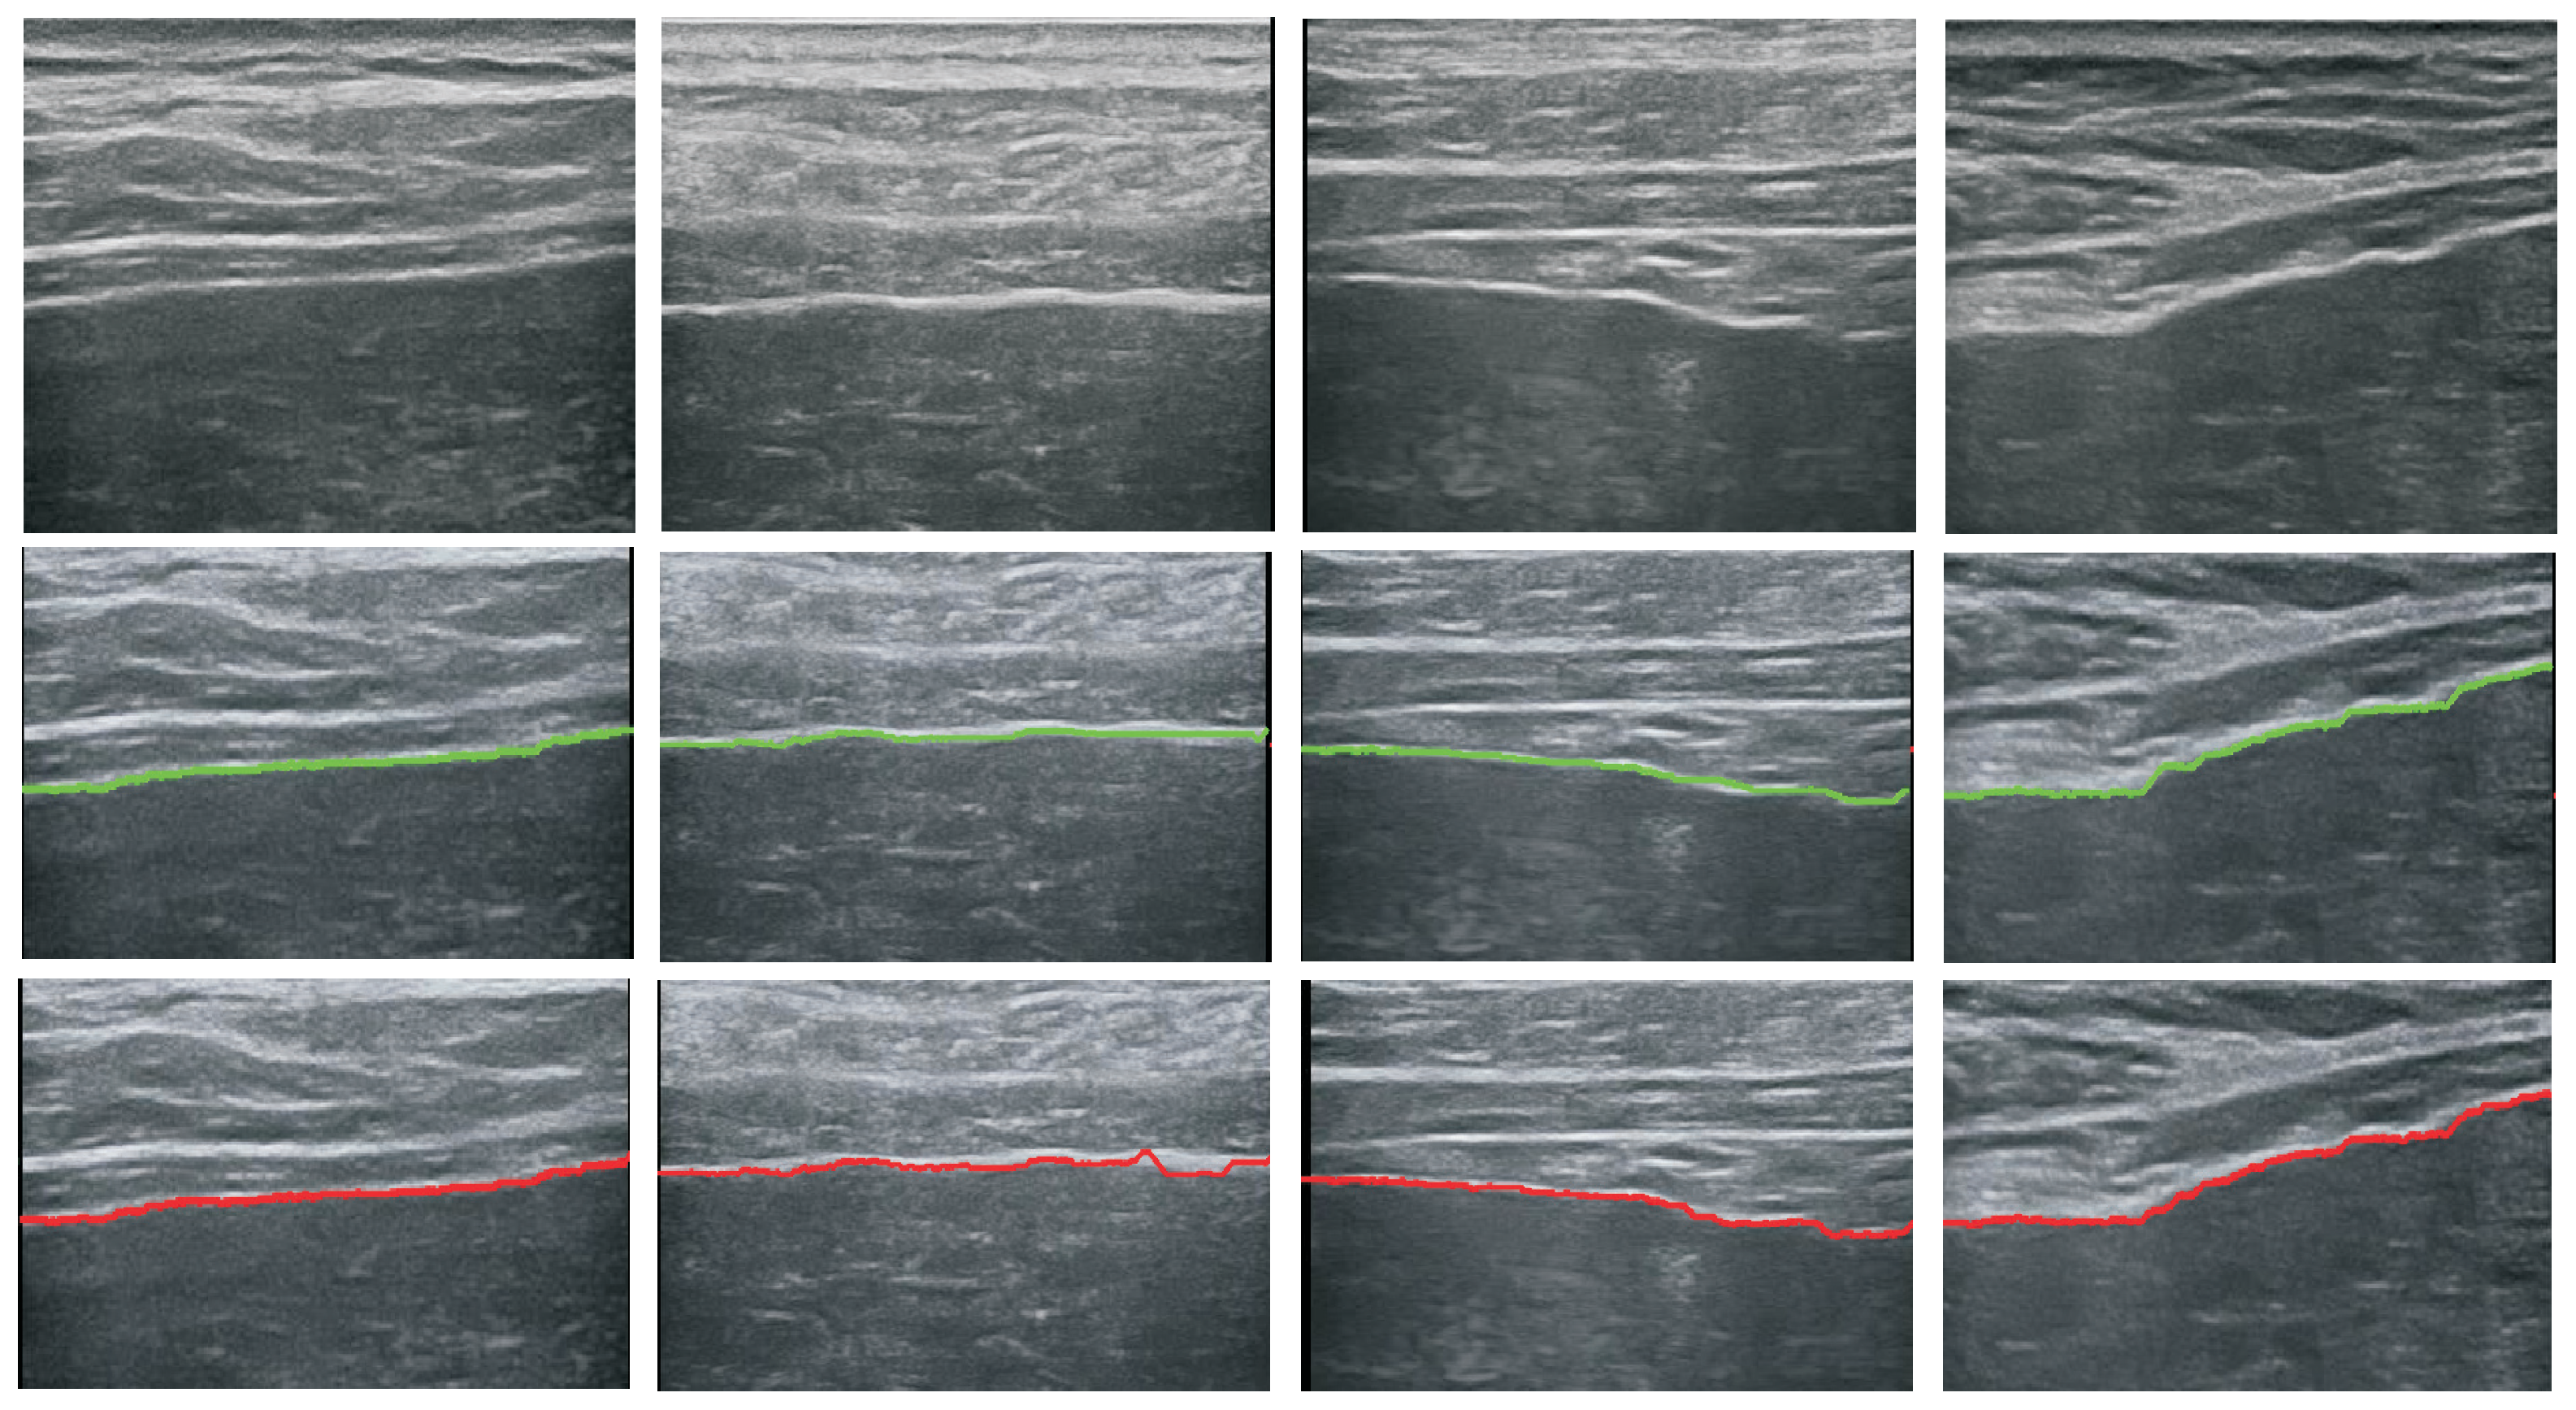

5.1. Performance of the Detector

5.2. Performance of Image Classification

5.2.1. Impact of Detection Error